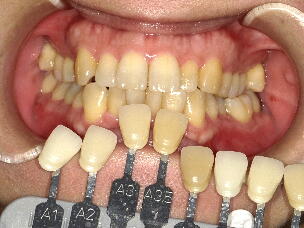

5.歯のホワイトニング ![]() ![]() ![]() ![]() ![]() ![]()

※歯のホワイトニングは期間、結果に大きな個人差があります。また歯の色が元の色に戻

っていく後戻りという現象も生じますので、詳細は歯科医師にご相談ください。